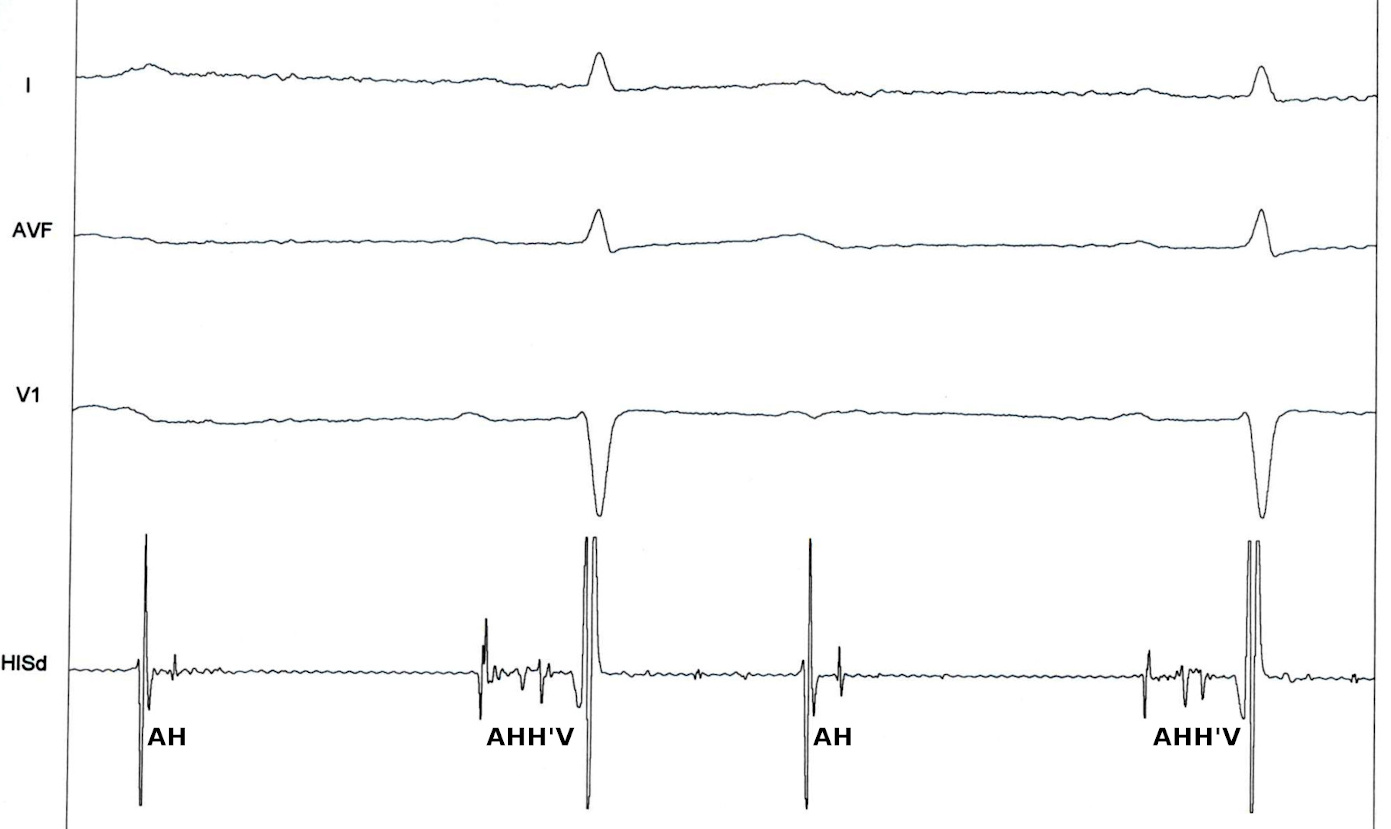

2:1 AV block

Asymptomatic - Diagnosis, level, management ?

2to1_intra_his.jpg

2to1_intra_his2.jpg